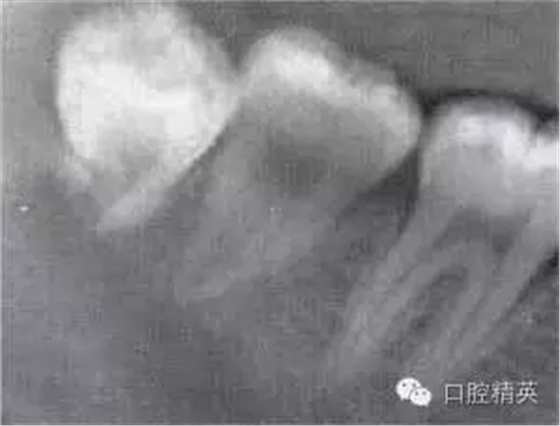

圖6-5 以上類(lèi)型的下頜第三磨牙由于根阻力小,一般不需分根,即可拔除。

A.合并根 B.短根 C.椎形根 D.牙根向遠(yuǎn)中彎曲 E.根分叉小 F.根尖未完全形成